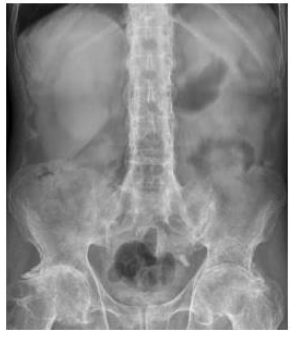

A inflamação que afeta os tecidos conjuntivos,

caracterizando-se pela inflamação das articulações da

coluna e das grandes articulações, como quadris,

ombros e outras regiões. Com o relato e a imagem

escolha a opção correta para esse problema

reumatológico.